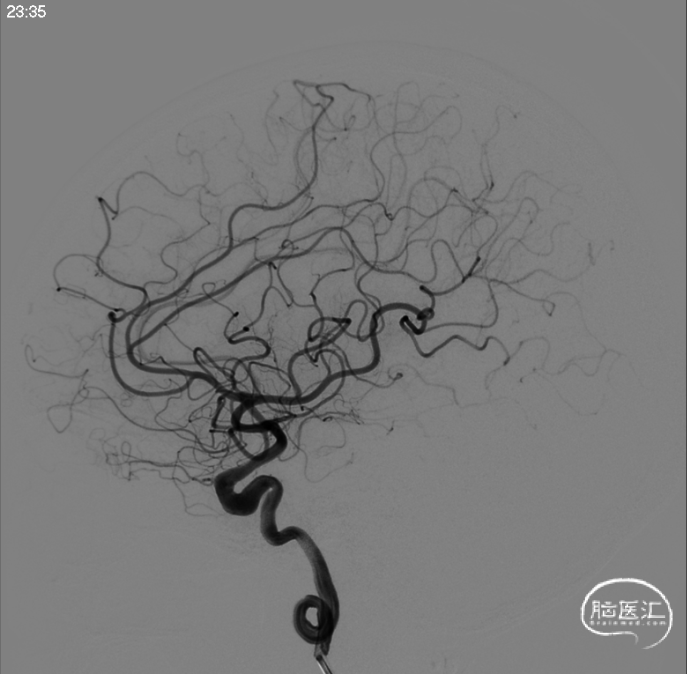

行正侧位造影及3D造影,全身肝素化后路图下将使用经塑形SL10微导管和prowler在0.14微导丝带领下超选进入动脉瘤和载瘤动脉,释放部分4.5*28支架,选用弹簧圈7枚栓塞动脉瘤,充分释放支架,造影复查显示动脉瘤被致密栓塞,载瘤动脉通畅。

成篮圈正位

成篮圈侧位

支架释放正位

支架释放侧位

栓塞结束工作位正位

栓塞结束工作位侧位

标准正位

标准侧位